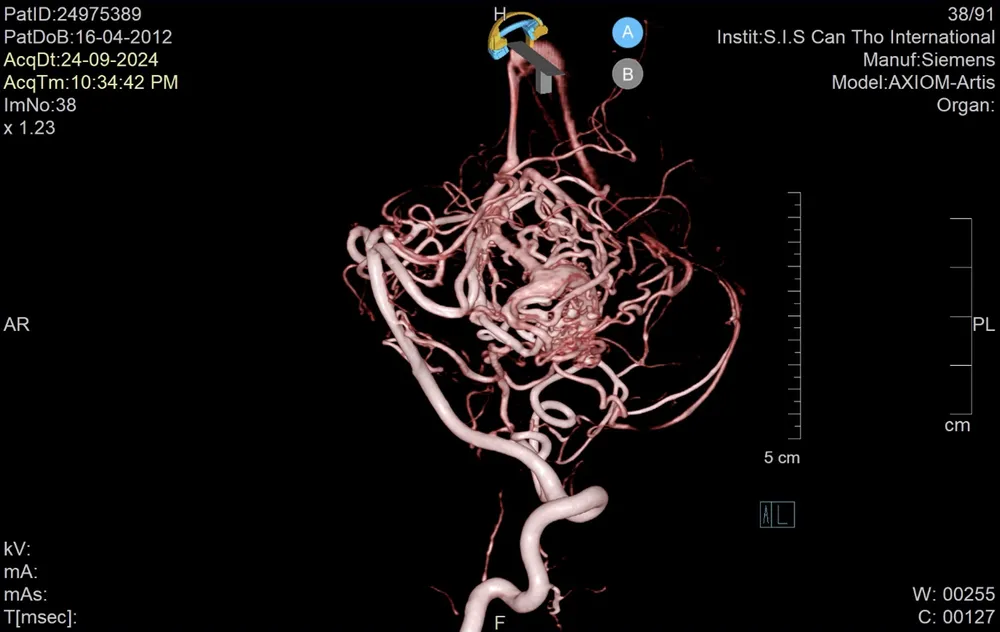

Tại Bệnh viện đa khoa Quốc tế S.I.S Cần Thơ, các bác sĩ tiến hành chụp DSA, ghi nhận có dị dạng thông động tĩnh mạch não (AVM) tiểu não trái, kích thước 15x30mm gây xuất huyết. Sau gần 1 giờ nỗ lực, đội ngũ bác sĩ đã can thiệp thành công bằng cách bơm keo sinh học giúp giảm lưu lượng máu vào khối AVM.